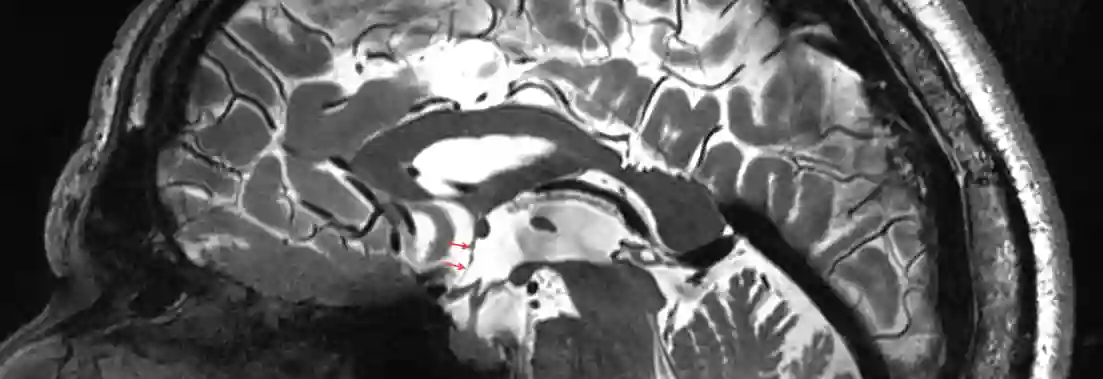

Dritter Ventrikel Sagittal

Sagittaler Schnitt durch den dritten Ventrikel. Abbildung adaptiert von Albert Rhoton 2002 in Neurosurgery.

Lamina terminalis im MRT

Darstellung der Lamina terminalis (rote Pfeile) in einer sagittalen T2 Sequenz eines 7 Tesla MRI.